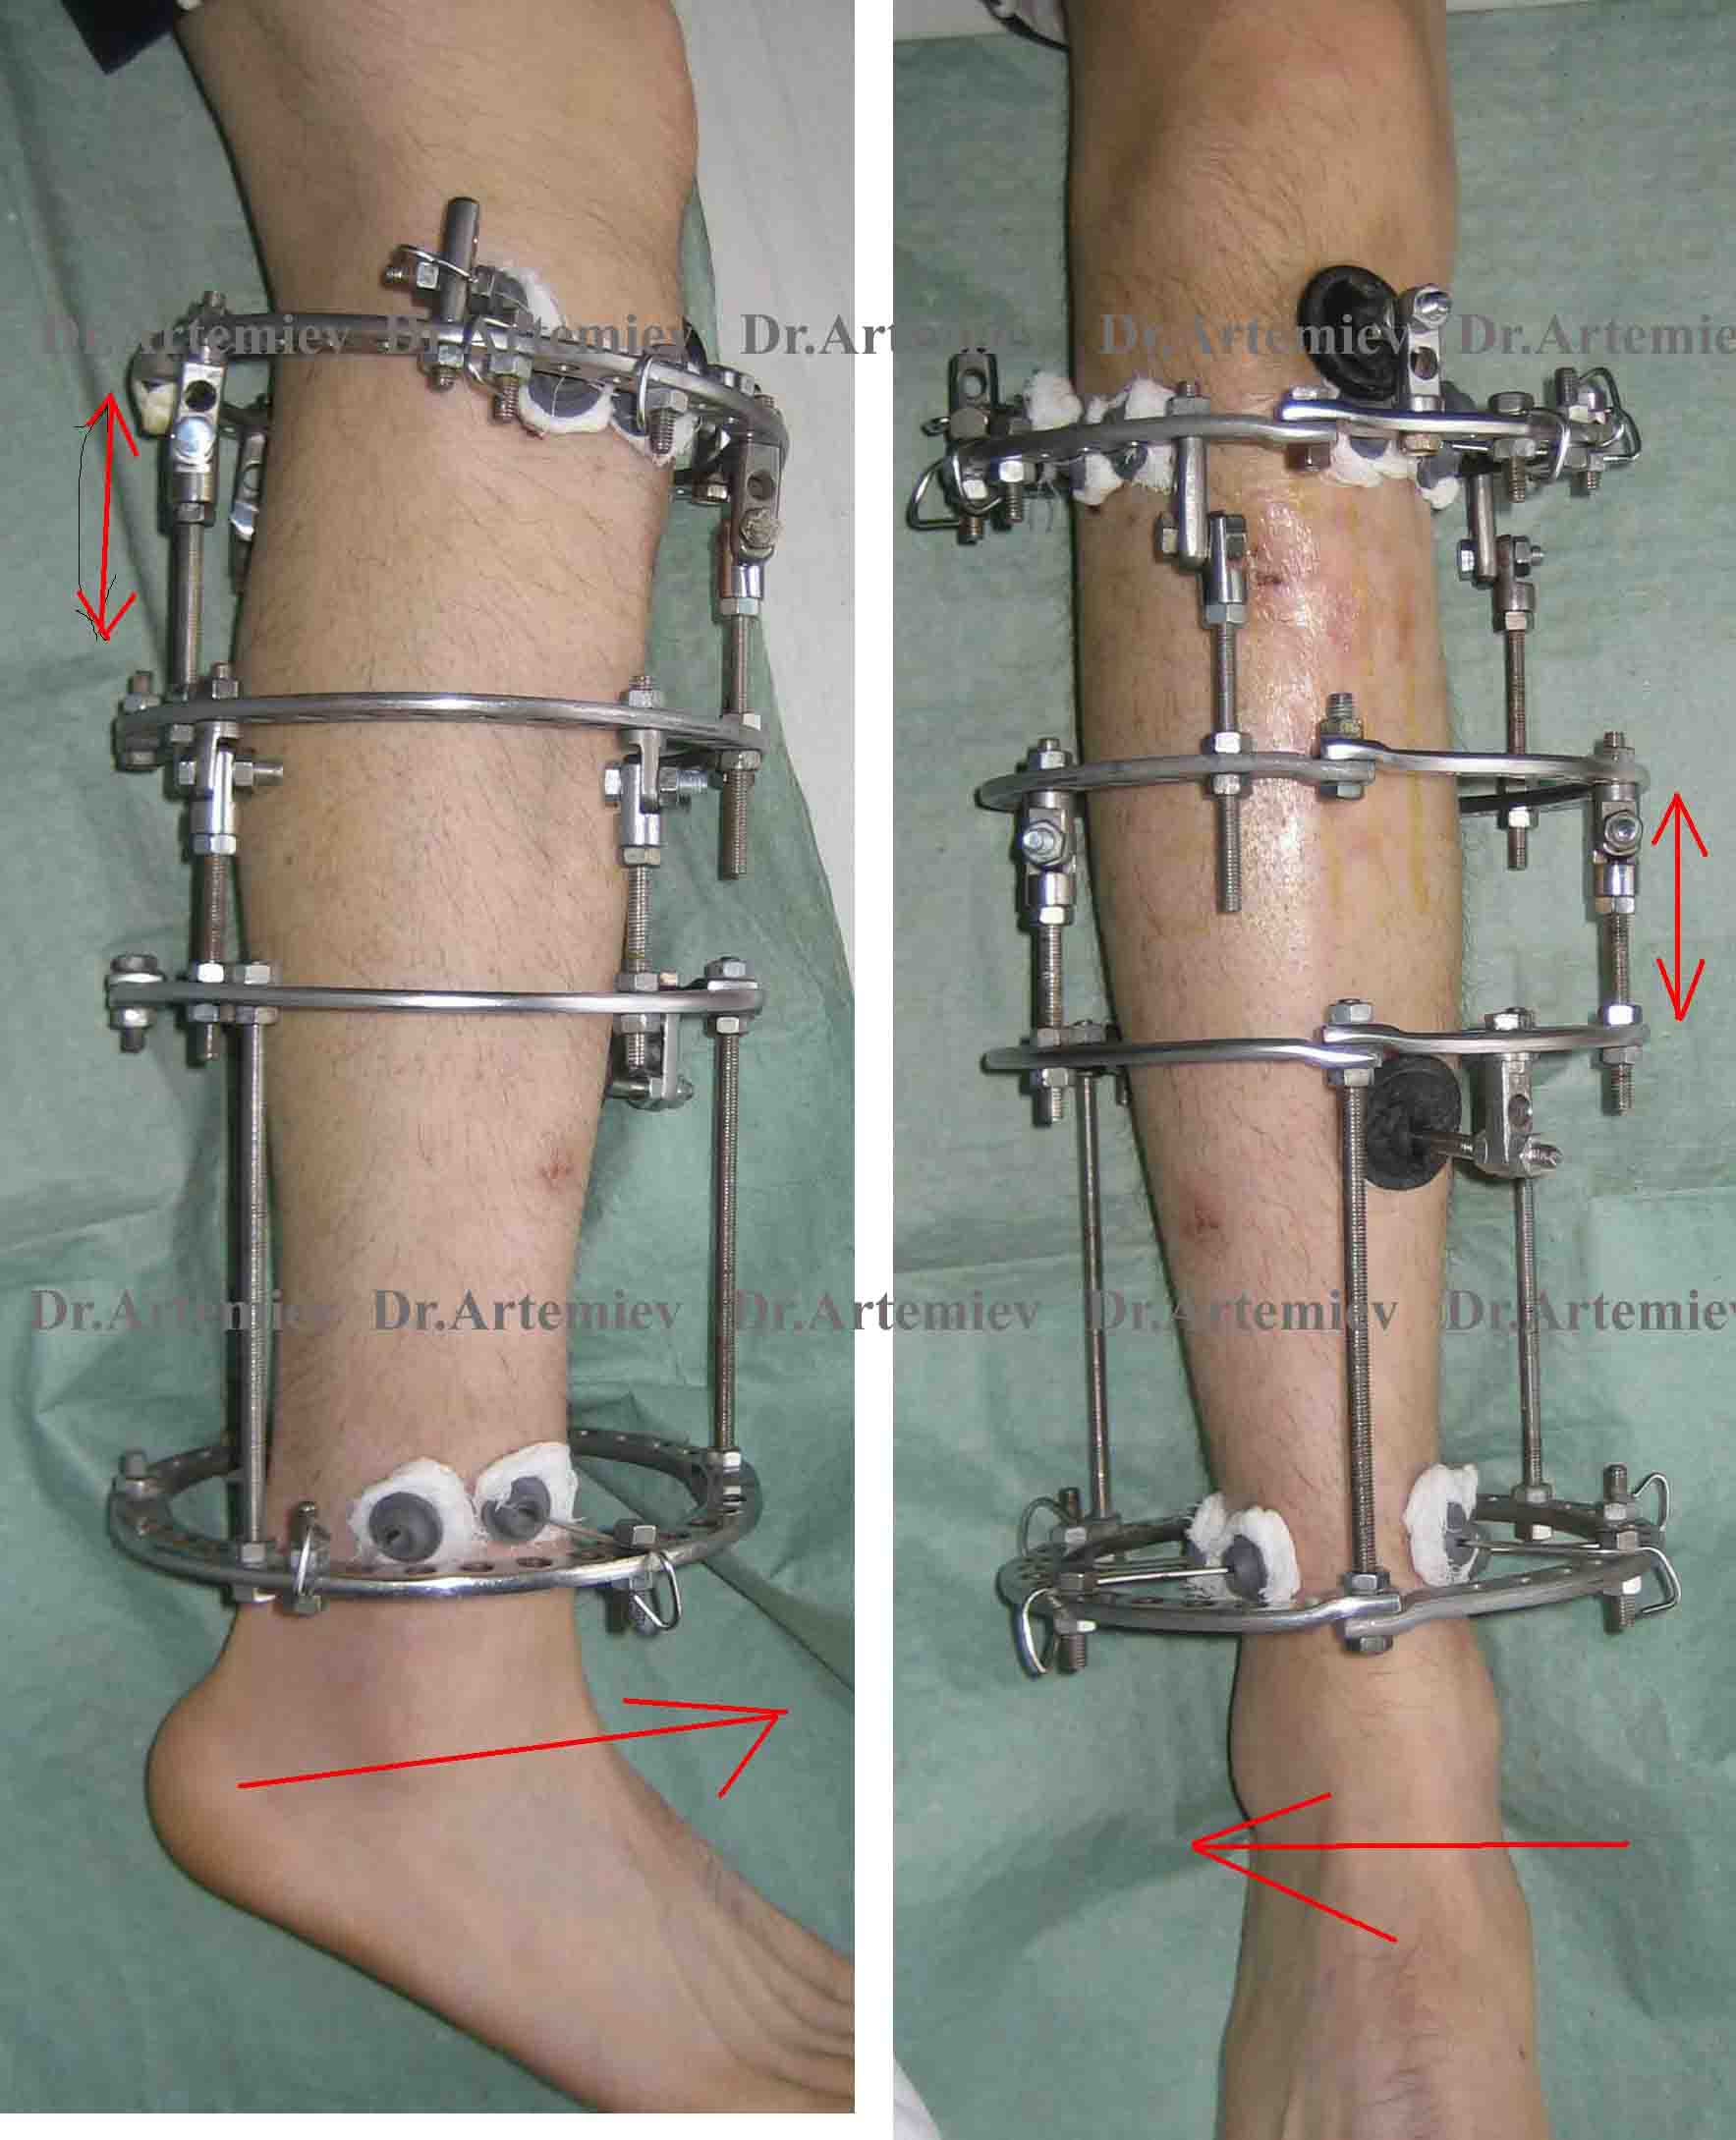

Аппарат Илизарова: принцип работы и применение